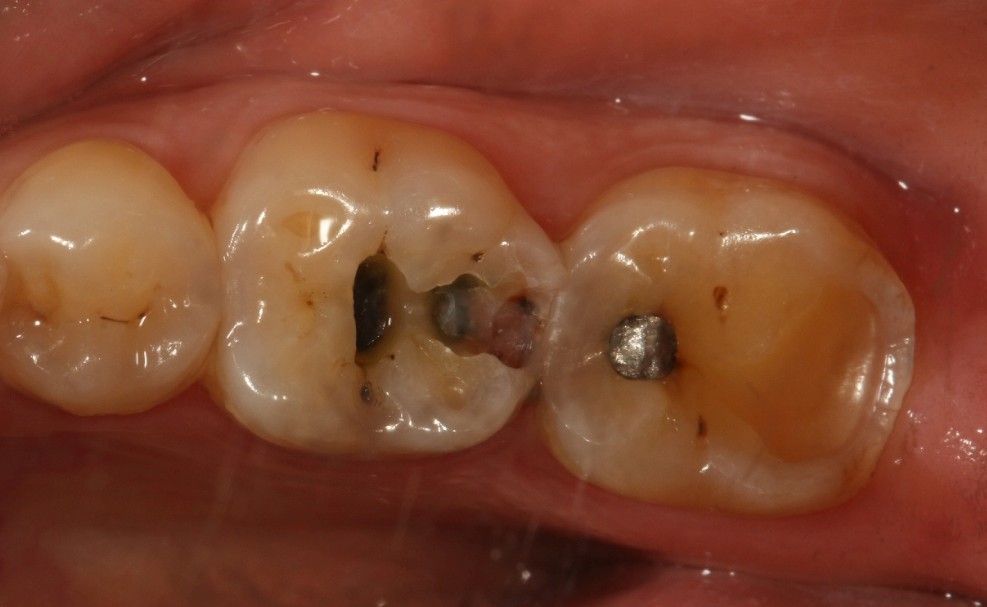

口腔检查时,会经常遇到以前补的银汞合金边缘变色,探有卡顿,形成了继发龋坏,建议重新充填或者瓷嵌体修复;瓷嵌体修复技术,可以非常好的恢复牙体形态和非常密合的边缘,色泽也非常逼真;我们采用CEREC(德国瓷睿刻)椅旁加工技术,达到最佳修复效果!